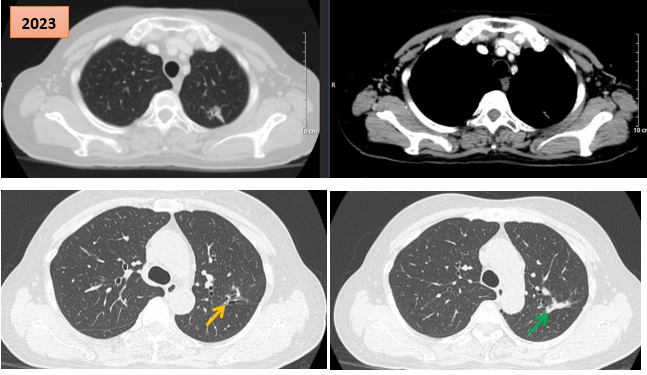

Hình ảnh cắt lớp vi tính theo dõi trong quá trình điều trị, tổn thương xơ hóa tại vị trí u cũ (mũi tên xanh) và giãn khu trú các nhánh phế quản liền kề (mũi tên vàng)

Bệnh nhân tiếp tục được theo dõi và điều trị duy trì bằng erlotinib. Đến thời điểm đánh giá lại vào tháng 5/2023, sau 6 năm điều trị liên tục, bệnh nhân vẫn trong tình trạng ổn định: Không đau ngực, không khó thở, các chỉ điểm khối u CEA và Cyfra 21-1 duy trì trong giới hạn bình thường.

Kết quả chụp CT ngực – bụng và cộng hưởng từ sọ não không ghi nhận thêm tổn thương mới. Tại vị trí u cũ, tổn thương xơ hóa gây co kéo rãnh liên thùy và giãn khu trú các nhánh phế quản lân cận, song không ảnh hưởng đến chức năng hô hấp và không gây triệu chứng lâm sàng.